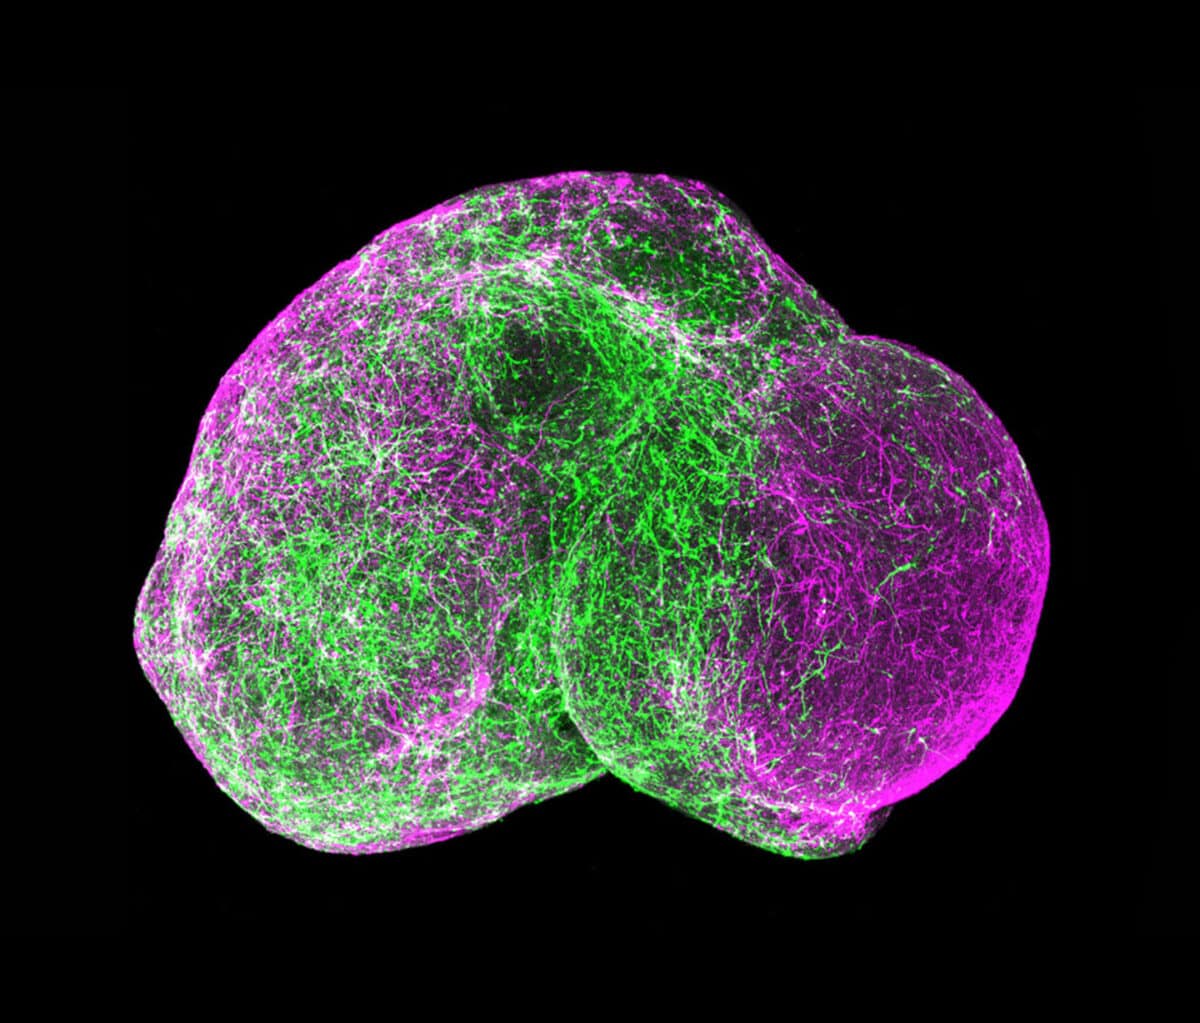

One way around that problem is to work with another kind of 3D cell culture known as a spheroid, which hasn’t yet gone too far down the path of development and still contains mostly identical, similarly differentiated cells.

Much of the work geared toward drug discovery and testing uses spheroids. Lee Rubin, professor of stem cell and regenerative biology at Harvard University, employs them to study spinal muscular atrophy (SMA), a neurodegenerative disease affecting children that is similar to amyotrophic lateral sclerosis (ALS) in adults. “Because I’m interested in developing therapeutics, I need a system that generates billions of human neurons that have the particular mutations for this disease,” he says. Those neurons need to be identical to each other, and to achieve that consistency, Rubin and his colleagues are willing to sacrifice some of the structural complexity they could get with more fully formed organoids. He can control what the spheroids’ cells become—muscle neurons or glial cells, or even muscle or gut cells—by adding particular chemical cues to the medium in which they grow. But because the spheroids were created from a cell carrying the SMA gene, all of the cells, of whatever type, also have that mutation.

Rubin first used spheroids to confirm that, as expected, motor neurons die if they have the disease mutation. “But we also discovered something surprising,” he says. Researchers had assumed that the SMA gene, essential for the survival of motor neurons, affected only that particular type of neuron. But the SMA mutation also generated defects in the other tissue cells—for muscles, gut, lung and thyroid—he derived from the iPS cells they used. That suggested that children with SMA might also suffer other problems affecting muscle tone or digestion, for example, that hadn’t been known or discussed.

The Rise of the Organoid Learning how to grow these tiny, rudimentary organs required a long series of discoveries, with contributions by a global contingent of research teams. 1951A lab at Johns Hopkins Hospital in Baltimore keeps a strain of human cancer cells alive and propagating indefinitely outside the body. Repeating this feat with normal cells proves more difficult. 1998Researchers at the University of Wisconsin isolate human embryonic stem cells, which renew indefinitely outside the body and can become the precursors to different tissue types. 2003Adult stem cells are isolated from the human mammary gland. These can also self-renew and differentiate into breast cell lineages. They are maintained in a 3D culture using Matrigel. 2007A team at Kyoto University in Japan show how to make embryonic-like cells from human skin cells, obviating the need to use human embryos and reinvigorating human cell culture research. 2011Hans Clevers at the Hubrecht Institute in the Netherlands grows human intestinal organoids using stem cells. They mirror key structural and functional features and can be used to model several disorders. 2012At the Austrian Academy of Sciences in Vienna, a group produces the first brain organoids. They use the tissue to study microcephaly, a disease that in humans causes abnormally small heads and brains. 2015Following the Zika virus outbreak in South America, several teams of researchers use the Austrian method of creating brain organoids to determine if and how the virus causes microcephaly. 2016Neuroscientists use organoids to model later stages of brain development, and show that multiple brain organoids can be fused to replicate more complex functions.

That ability may come in the next frontier of organoid development, as researchers look to culture various types of stem cells together to create organoids that incorporate additional features. For example, adding endothelial cells of blood vessels to the initial cells of a culture might enable organoids to spontaneously create a working vascular system. Researchers are also beginning to “fuse” different organoid types to approximate the kinds of linked systems Ingber achieves with organs-on-chips.